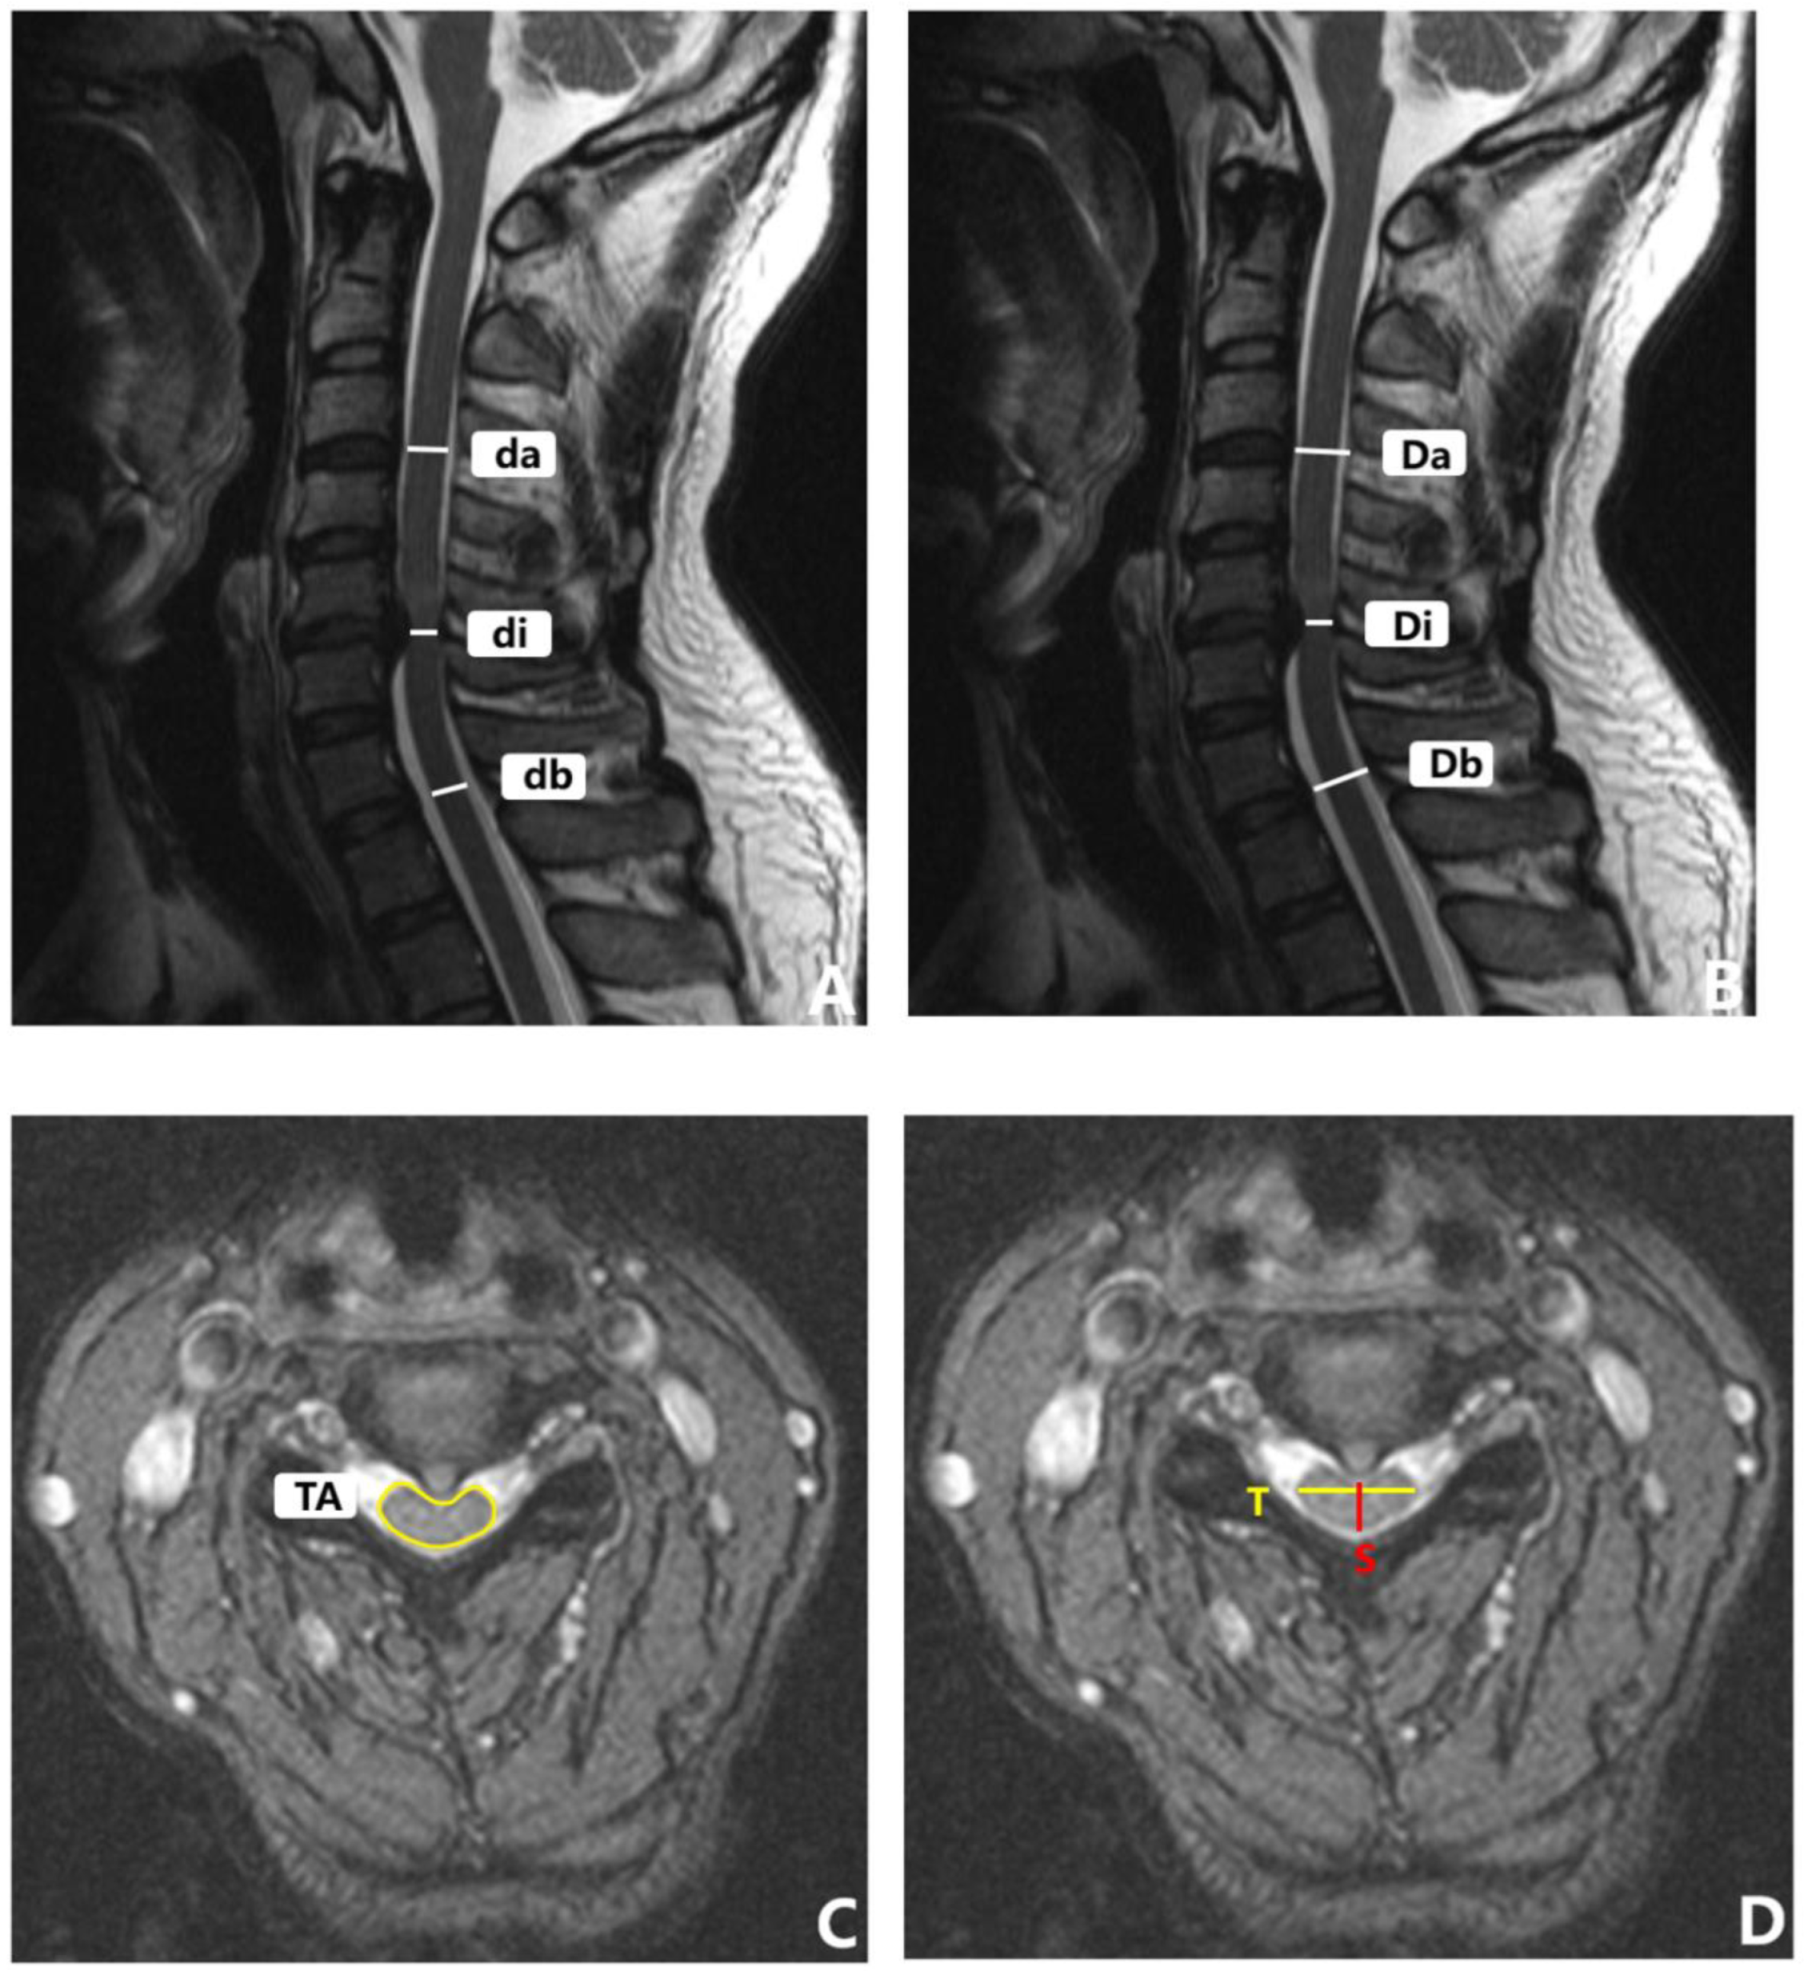

(3) Imaging parameters. For the lateral cervical radiographs, standard radiographic techniques were applied. The tube-to-subject distance was 1.83 m and the radiographic tube was centered at the C4-C5 intervertebral disc space without magnification. Lateral radiographs of the cervical spine were taken when the patient was in a comfortable standing position; the upper extremities were positioned naturally at the sides of the trunk and the patient looked straight ahead.

Flexion (or extension) cervical radiograph. The patient stood sideways in front of the camera frame, the head and neck were maximally flexed (or extended), the long axis of the neck was parallel to the long axis of the film, and the shoulders were drooped as far as possible. The remaining requirements were the same as those of the lateral films. All of the above images were captured by the same imaging technician. The measurement methods of the cervical sagittal parameters in the radiographs are detailed in Table 1 and Figure 4. The range of motion (ROM) was calculated as the extension minus the flexion.

Figure 4.

Sagittal radiograph of cervical spine with representative measurements. (A) C2-C7 cobb angle (CL), T1 slope (T1S). (B) C2-7SVA.